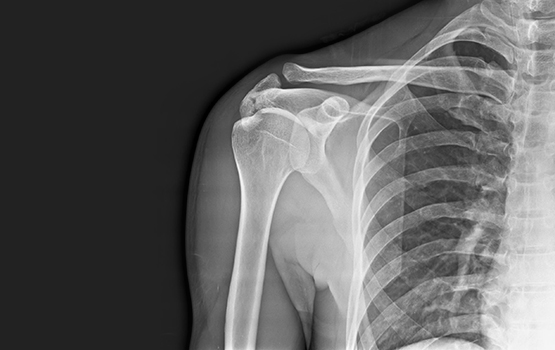

Shoulder Digital X-ray

An X-ray is a common imaging test that has been in practice since decades. X-rays provide doctors with an inside view of the body, without necessitating an incision. These images prove instrumental in diagnosing, monitoring and treating many medical conditions. At Aster, we have the latest Digital X-ray technology offering hi-definition imaging.